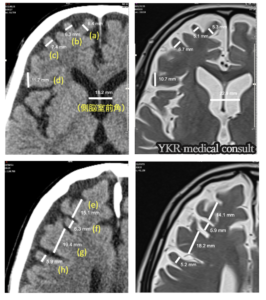

④脳回幅計測と側脳室前角幅計測

左:交通事故受傷時 右:事故後約2年8か月後

さらに、被告側医師意見書では触れられていなかった脳委縮について画像評価をもとに指摘をし(画像④参照)、その萎縮率から受傷時のびまん性軸索損傷を起因とする脳震盪後症候群の可能性を示し、交通事故と高次脳機能障害との因果関係があることを認めた。加えて、原告陳述書に記載された原告の素行について認知機能障害や精神機能障害を認め、長期間にわたり脳を圧迫していた左慢性硬膜下血腫の影響(呂律不良、説明困難等)が考えられることを意見した。

しかし、本件では脳萎縮の進行は画像上明らかであり、軽度のびまん性軸索損傷による脳震盪後症候群が主病態であると意見する。これに慢性硬膜下血腫手術前の頭蓋内圧亢進による両側大脳への影響および手術後も長期残存した左慢性硬膜下血腫による直接圧迫から発生する左脳の障害が加わったものであると考える。また、アルコール依存症や続発する肝障害により「脳機能の脆弱性」が存在しているという主張は本件における根拠に欠けると意見した。